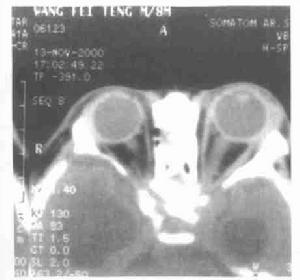

(二)影像檢查

X線檢查可了解骨骼改變以及眶腔和視神經管的變化良性腫瘤由於長期眶壓增高,可使眼眶擴大、骨質增生或吸收骨質破壞提示惡性腫瘤。平片如有鈣化斑見於視網膜母細胞瘤、血管瘤及腦膜瘤視神經孔擴大提示視網膜母細胞瘤已通過視神經向顱內轉移。視神經膠質瘤或視神經鞘腦膜瘤也可有此表現。超聲探查有較好的軟組織分辨力可顯示眶內脂肪、視神經、眼外肌和眼上靜脈如多個眼外肌肥大,肌內有較多回聲,常為GraVes病在強回聲光團中出現弱回聲或無回聲區,可作為腫瘤診斷標準。CT掃描具有較高密度分辨力和空間分辨力眶內病變如腫瘤、炎症和血管畸形均顯示高密度影,且眼內眶內和眶周結構均能顯示。磁共振成像與CT基本相同,其軟組織分辨力優於CTr照相機閃爍攝影和ECT可觀察細胞吸收、利用和排出核素的代謝過程,但因各病變對所吸收核素選擇性差除檢查轉移性癌之外,很少被採用。DSA選擇性血管造影是診斷動靜脈瘦觀察腫瘤供血狀態必不可少的檢查方法。

CT掃描(一)眼眶蜂窩織炎

是眶內軟組織或骨膜下的急性炎症由於眶和顱腔、眼球的密切關係,可以引起永久性視力障礙和顱內併發症多由鄰近組織的感染擴散,或外傷感染所致。臨床表現為眼球突出及運動障礙並有眼瞼紅腫、球結膜充血水腫,眼底可有視乳頭充血水腫及視網膜水腫。重者體溫增高,白細胞增多由於心一眼反射,可能出現相對的緩脈。眶內炎症可通過靜脈眶上裂波及海綿竇可形成海綿竇栓塞。其眼部表現和蜂窩織炎相似,但較蜂窩織炎的中毒症狀重迅速波及對側,出現頭痛、煩躁不安譫妄、驚厥、昏迷等顱內病變症狀有些眶內惡性腫瘤除眼球突出外,也可有眼瞼紅腫、眼球運動受限與眶蜂窩織炎難以鑑別。故應重視病史及全身體格檢查,影像學檢查有助診斷